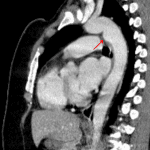

- Incidental small ductus diverticulum

- Ductus diverticulum (anatomic variant)